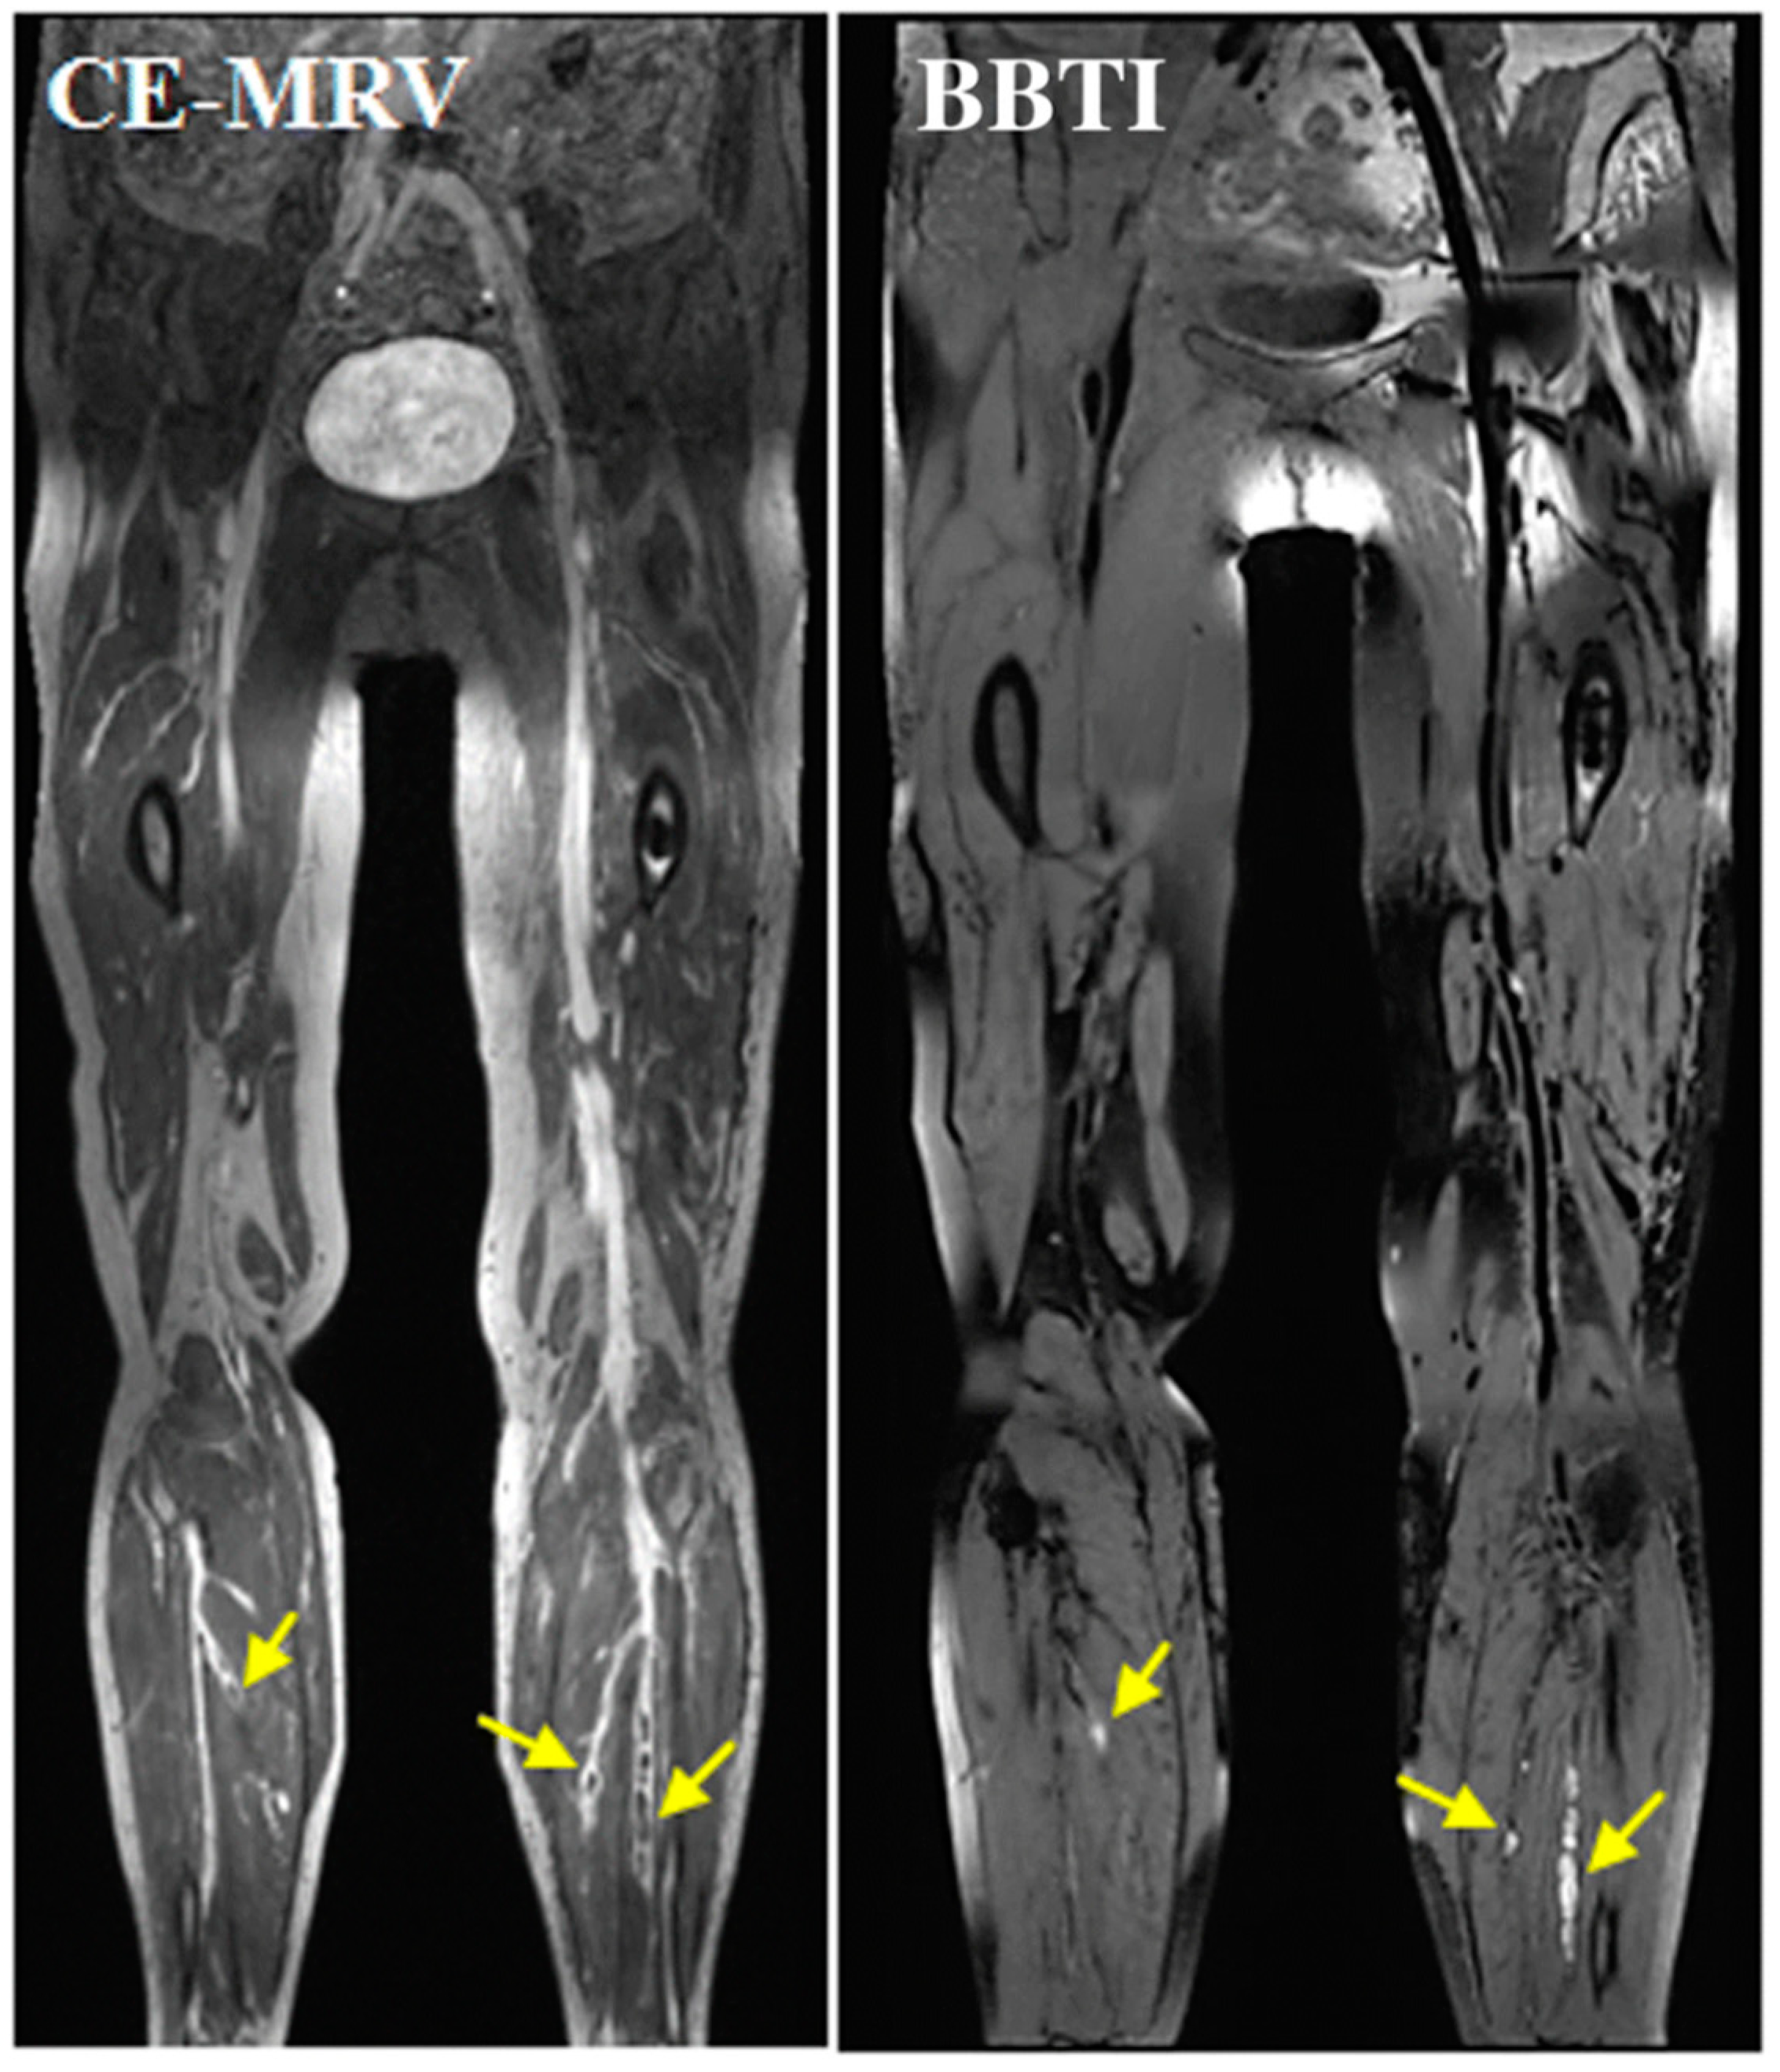

- Chen, H.; He, X.; Xie, G.; Liang, J.; Ye, Y.; Deng, W.; He, Z.; Liu, D.; Li, D.; Liu, X.; et al. Cardiovascular magnetic resonance black-blood thrombus imaging for the diagnosis of acute deep vein thrombosis at 1.5 Tesla. J. Cardiovasc. Magn. Reson. 2018, 20, 1556. [Google Scholar] [CrossRef]